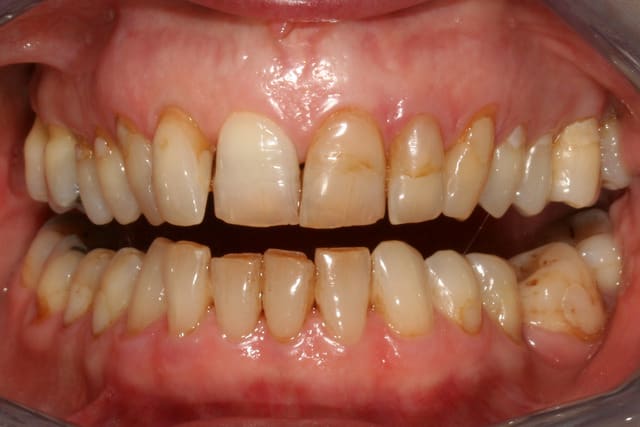

Si on regarde la photo 3, sourire de face, tu doit faire 10 céram en haut, de

5 à 5 (et là, je ne retiens pour pas dire 12...)

Ensuite, tu fais rien pour la couleur en bas ? OK

pour l'attrition ? OK, au pire une goutière nocturne.

Si tu touches 6 dents (3 à 3), ben le sourire ne sera tjs pas trop beau...juste mon pt de vue.